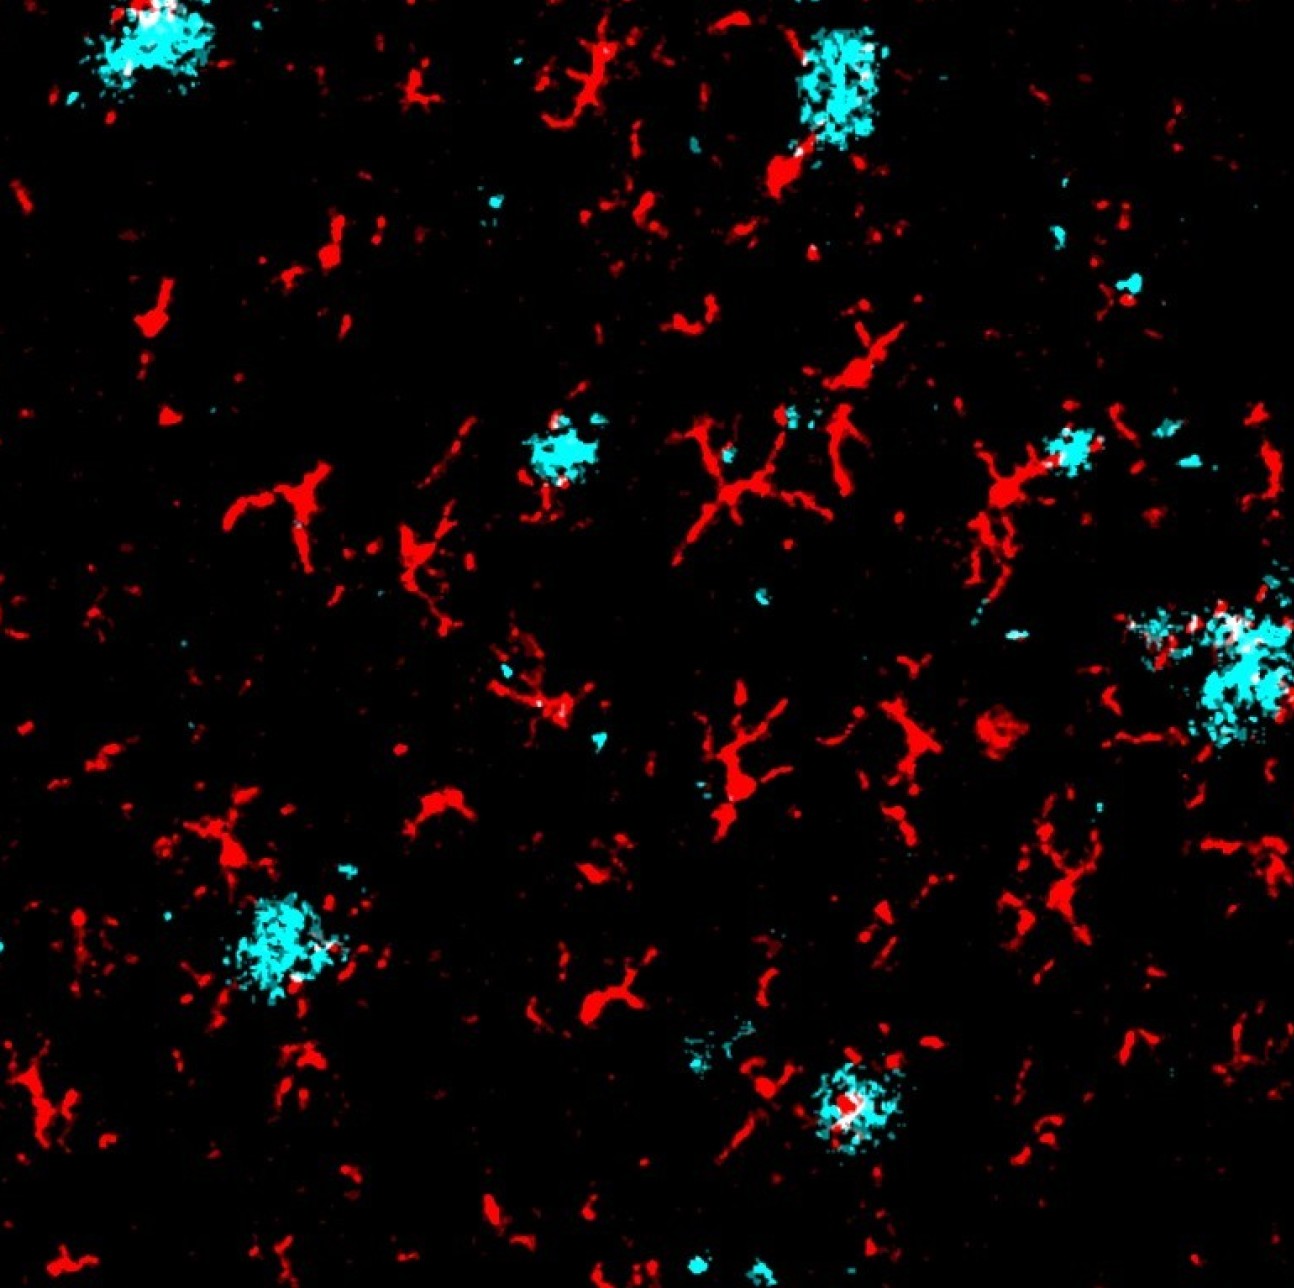

Microglia and Amyloid Plaques - Callum Muirhead and the Multi-Omics Atlas Project team

"Imaging mass cytometry image of amyloid plaques (red) and microglia (cyan)."

"Co-localization of amyloid plaques and microglia (white)."

"Co-localization of amyloid plaques and microglia (white)."